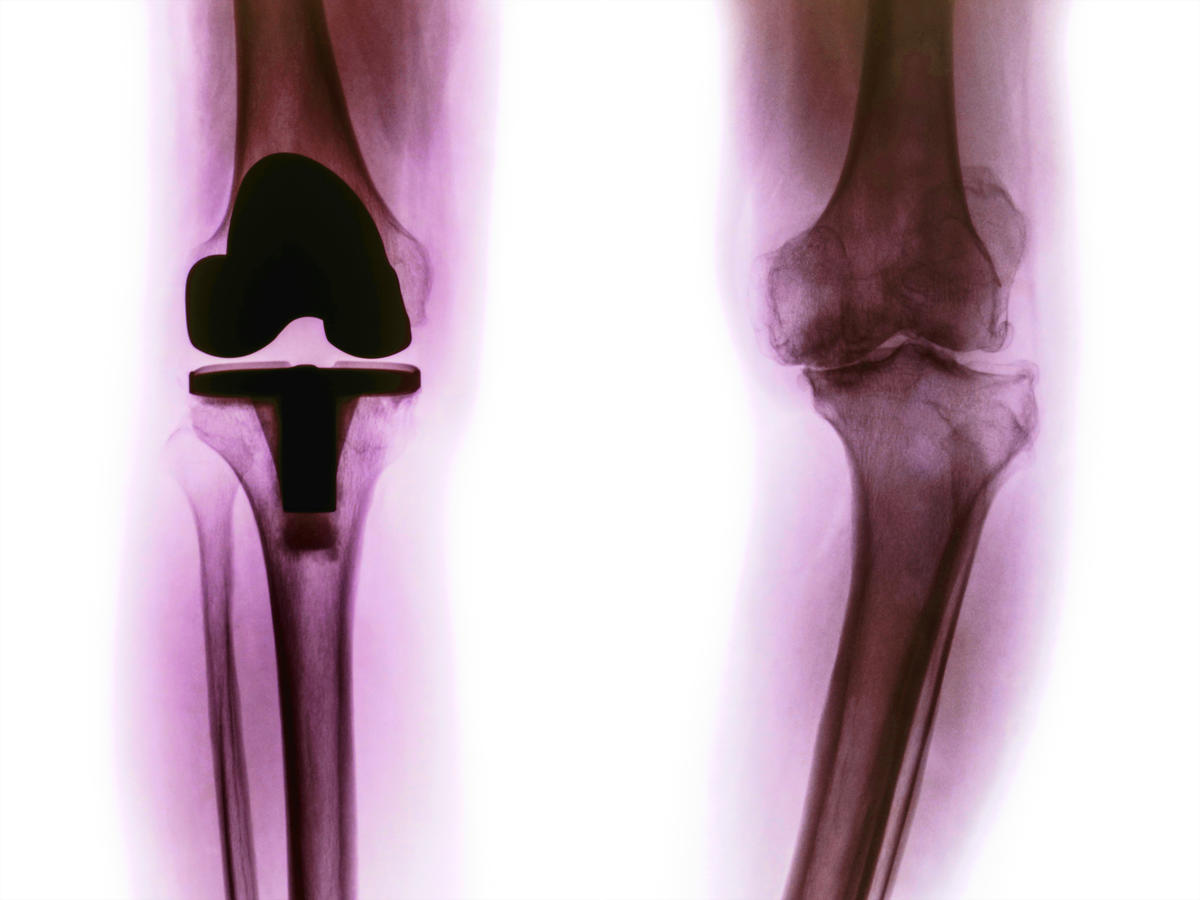

Implantable medical devices, ranging from artificial knees to cardiac pacemakers to deep brain stimulators, offer substantial benefit to patients and value to society. This clinical and social value depends, however, on the high quality but affordably priced devices being used on the appropriately selected patient, by an experienced surgeon, and in the least costly site of care. Over the past ten years BCHT has conducted a series of quantitative and qualitative studies of device assessment, pricing, and utilization, with the results disseminated through peer-reviewed journal articles, Issue Briefs and journalistic reports, and presentations at professional, governmental, and scholarly conferences. Some of the key findings of the research were brought together in a book, Purchasing Medical Innovation, published by the University of California Press in 2015.

The life sciences industry creates a remarkable pipeline of new medical devices, but these too-often are used on the wrong patient, at the wrong time, or at the wrong price. The way to sustain innovation while ensuring affordability is to improve the process of product assessment and purchasing. Purchasing Medical Innovation analyzes the roles of the Food and Drug Administration (FDA), Medicare and private insurers, physicians and hospitals, and consumers themselves in the larger process of assessing performance, price, and appropriate use. The book is short (150 pages) and written in a non-technical style targeted at managers and professionals in hospital systems, health plans, and life sciences firms, regulatory agencies, and consumer advocacy organizations.